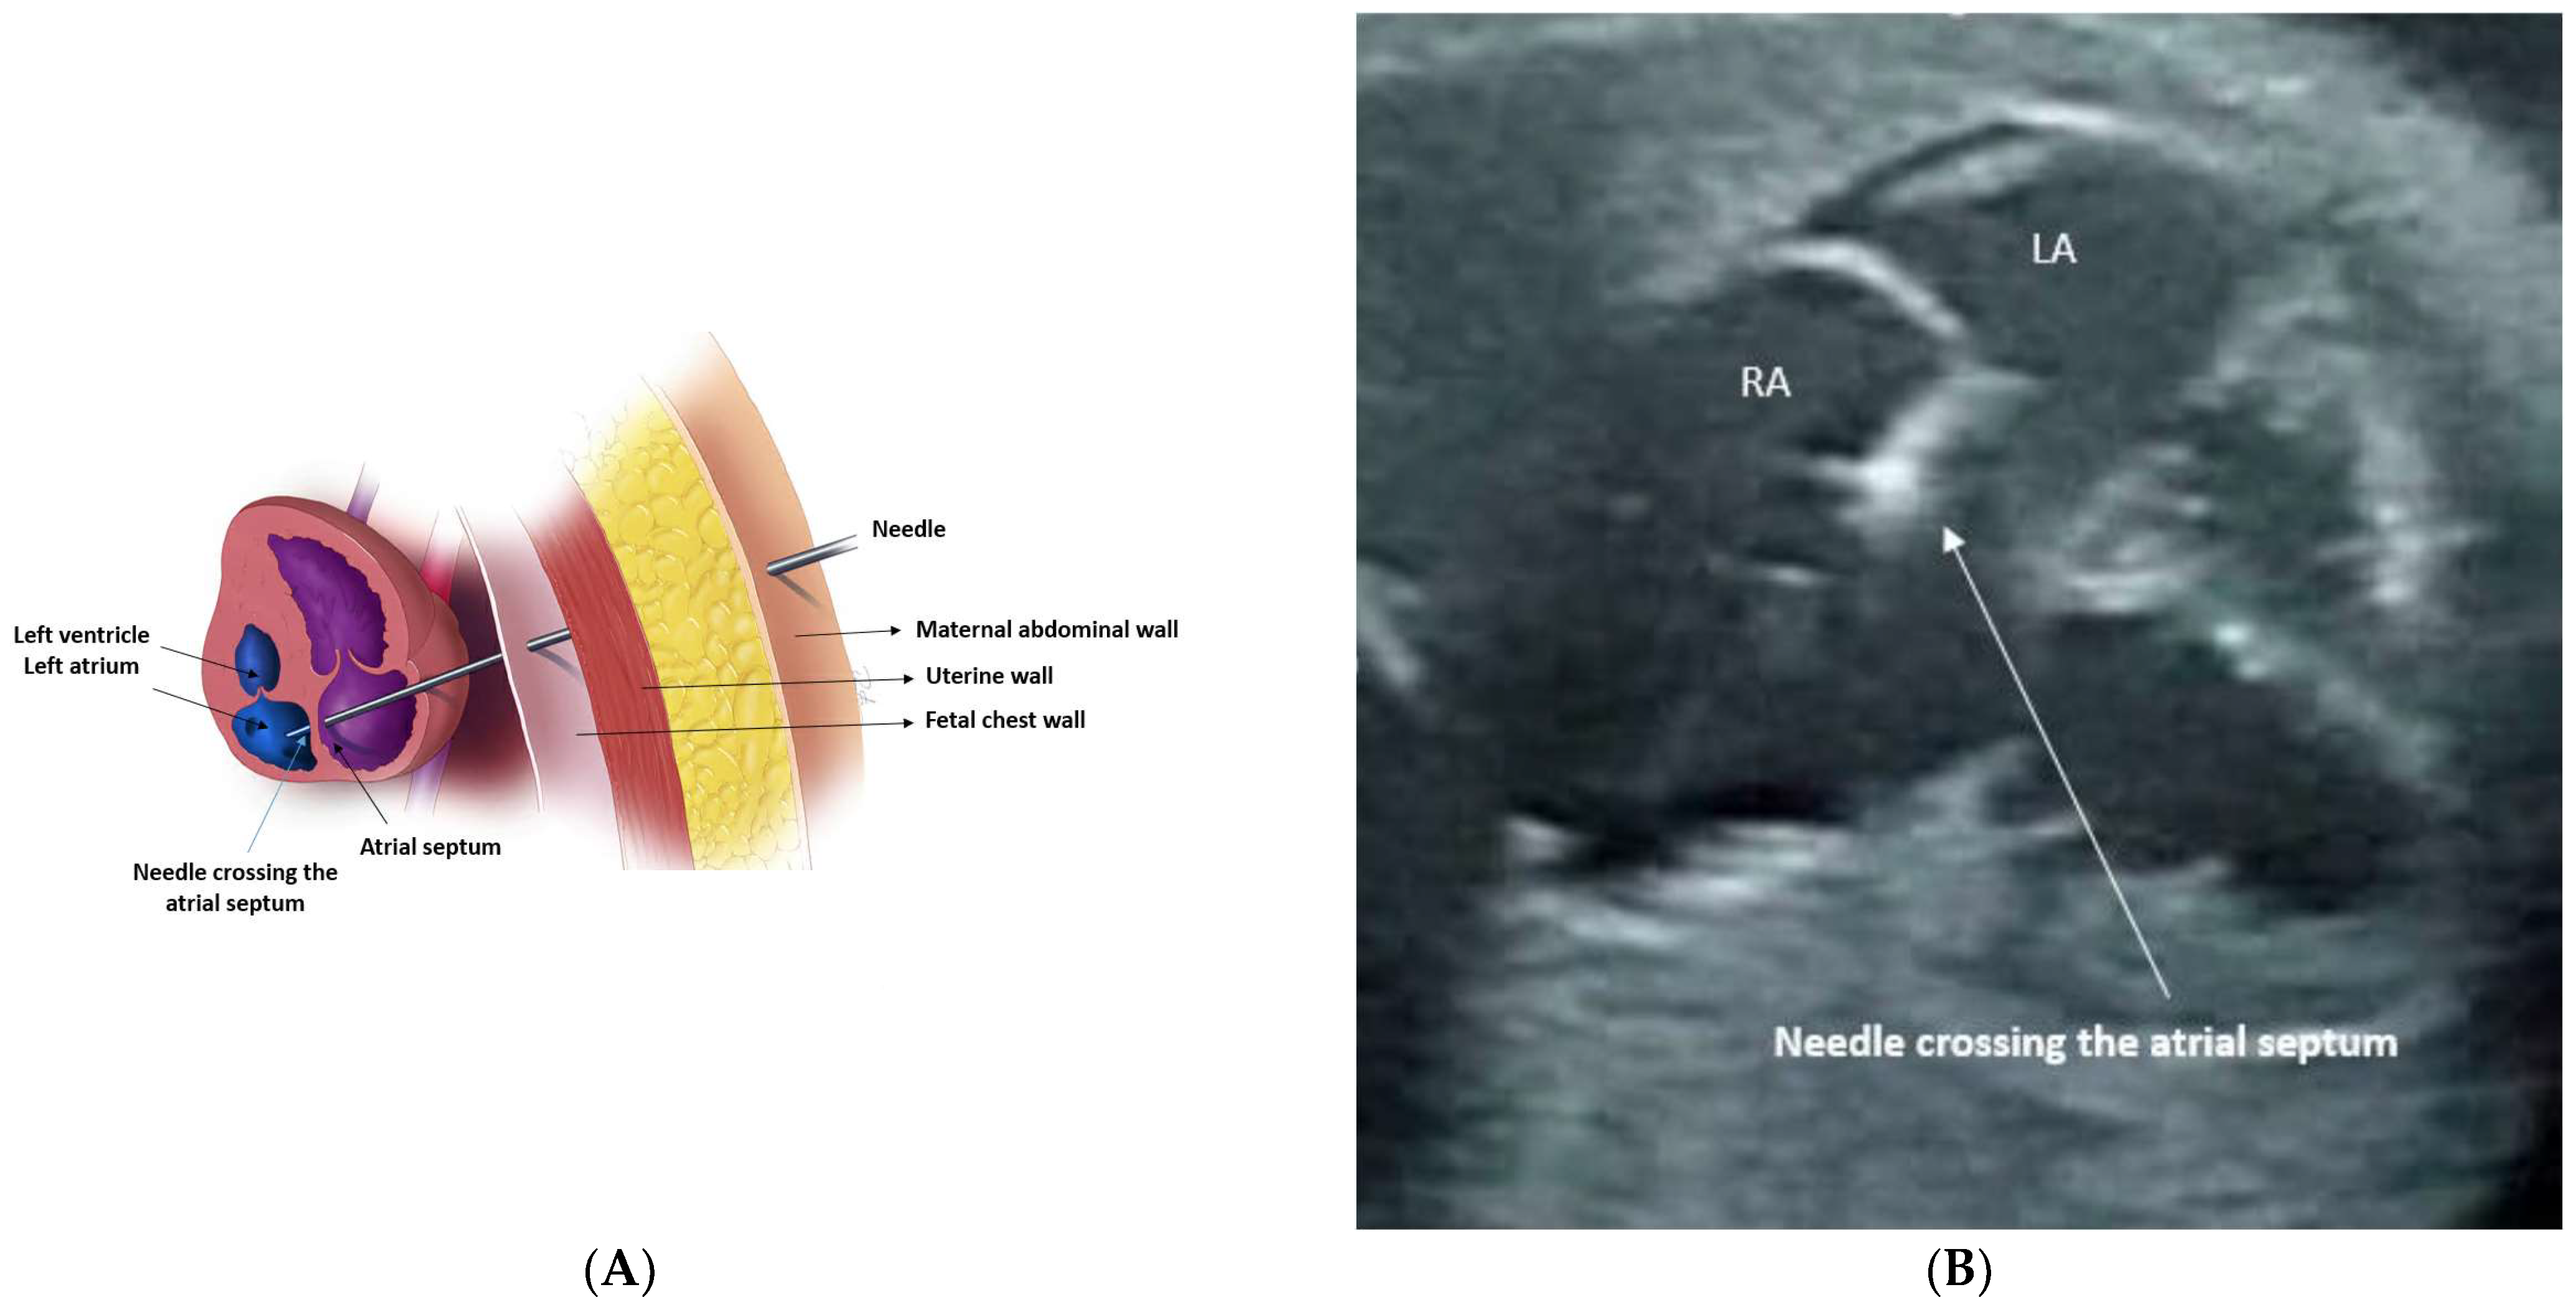

3.2. Procedural Technique